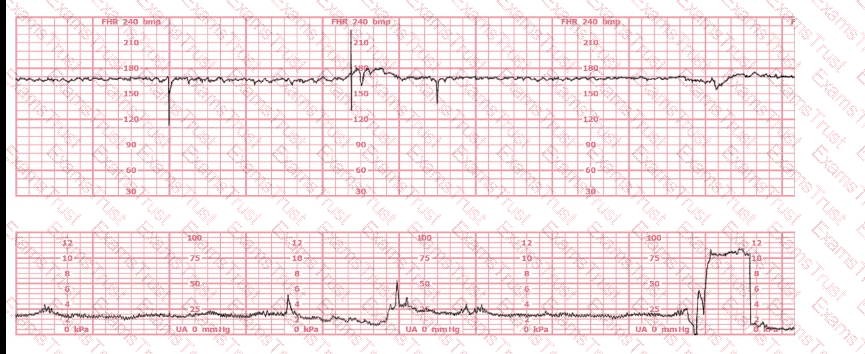

This tracing is consistent with:

The most probable underlying fetal physiologic cause for this tracing would be:

This patient received an epidural 15 minutes prior to the tracing shown. The next course of action is to: